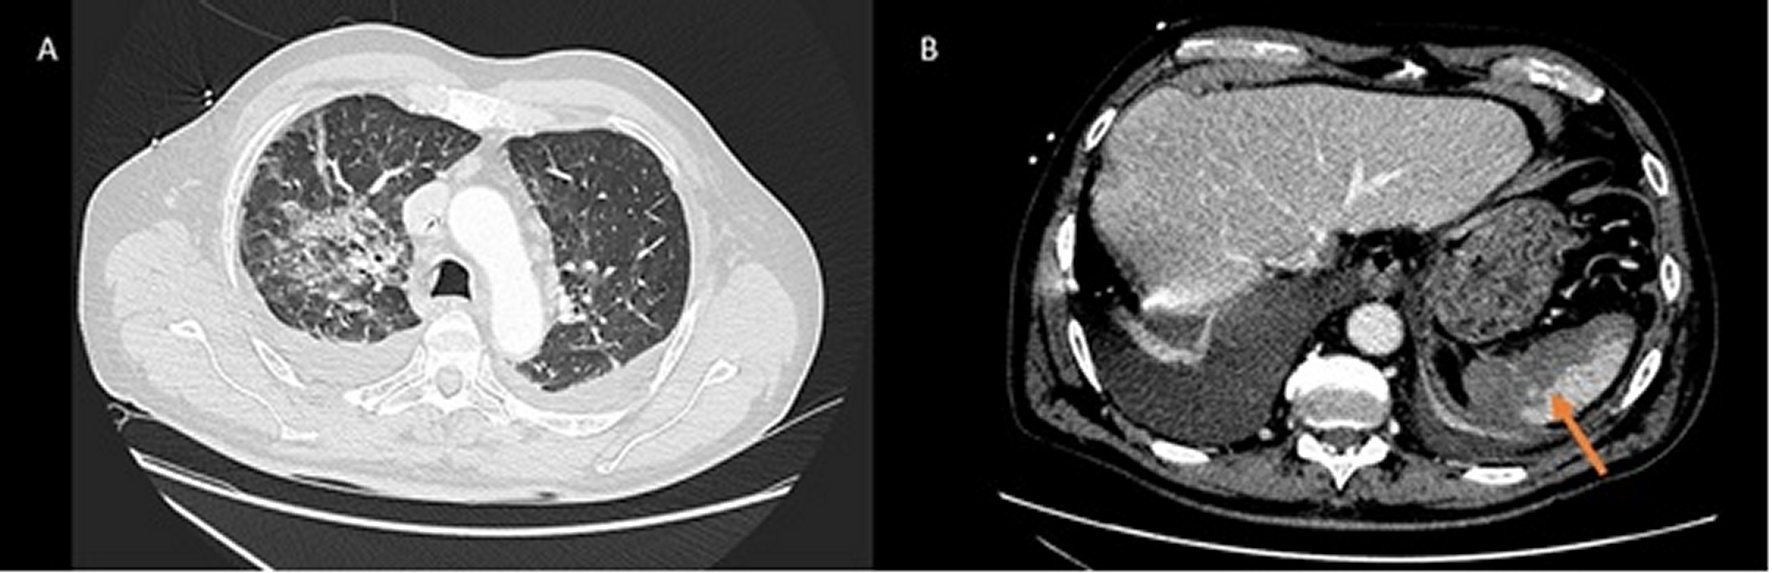

The Microbiology service reported the growth of Capnocytophaga canimorsus in the blood cultures. These cultures were positive in the first 24 hours. The bacteria were identified by mass espectometry (MALDI-TOF). The patient being interrogated again and referred that he was in contact with dogs and he sustained scratches and a light bite wound 4 or 5 days ago. During the first days, the evolution from a clinic point of view was bad, with arterial hypertension, requiring continuous perfusion of clevidipine. Additionally, the patient kept anuria and needed nasal oxygen therapy of high flow, due to his respiratory distress. From the analytic point of view, the kidney function, continued with severe platelet count, despise the transfusion of 3 platelet pooles, increase in bilirubin and LHD (see analytic evolution in Table 1). In light of the deterioration, a continuous renal replacement therapy began and a contrast Thoracoabdominal tomography was made. Ground glass infiltrations were observed in both pulmonary parenchyma and the lack of contrast of a significant proportion of the splenic parenchymal, radiologically compatible with infarct (Figure 1).